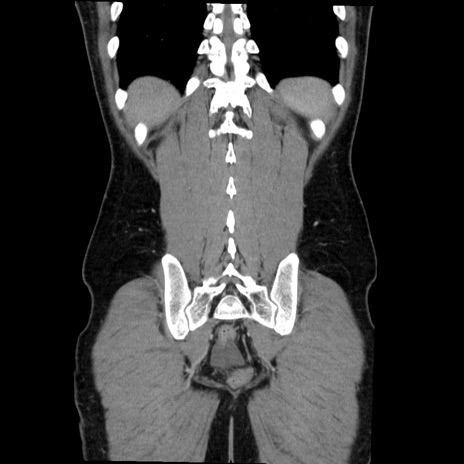

症例36(冠状断像)

【症例】20歳代 男性

【主訴】心窩部痛

【現病歴】今朝より上腹部痛あり。一旦軽快していたが再度出現したため救急要請。昨日夕に白身の魚を含む刺身を食べた。

【身体所見】BP 136/89mmHg、HR 74/min、BT 37.0℃、腹部:膨満、軟、心窩部に圧痛あり。反跳痛なし、筋性防御なし、腸雑音やや亢進あり。

【データ】WBC 17700、CRP 0.48